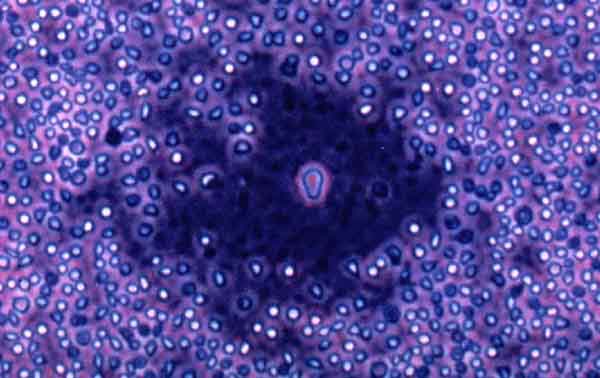

linfociti B

Non si tratta di un vaccino preventivo ma somministrabile a scopo curativo a pazienti gia’ colpiti dalla malattia. L’obiettivo e’ combattere il linfoma Non-Hodgkins, che colpisce alcuni tipi di globuli bianchi, i linfociti B che, hanno spiegato gli esperti, reagiscono in modo specifico nei confronti degli agenti estranei al nostro organismo (antigeni). Ogni linfocita possiede sulla membrana una proteina (immunoglobulina) in grado di riconoscere gli antigeni. Nell’insorgenza del linfoma Non-Hodgkin, le cellule tumorali hanno origine da un singolo linfocita B che, ”impazzendo”, si riproduce senza controllo. Ecco quindi, hanno proseguito gli esperti, che il vaccino ‘su misura’ deve avere come suo specifico bersaglio l’immunoglobulina accoppiata a quel linfocita B, inducendo, paziente per paziente, una risposta immunitaria specifica contro la sola immunoglobulina tumorale. Per questa ragione, sui pazienti verra’ effettuato il prelievo di alcune cellule tumorali per individuare il tipo di immunoglobulina coinvolta, identificarne il gene che la codifica e riprodurlo in laboratorio. Il vaccino a DNA risultante verra’ iniettato sotto la cute con una speciale pistola ad aria compressa e quindi comincera’ a stimolare la reazione immunitaria anti-tumorale. In particolare, il vaccino dovrebbe colpire le cellule tumorali residue e prevenire un’eventuale ricaduta, frequente nei linfomi. Il protocollo dell’esperimento prevede che ai malati venga somministrato il vaccino dopo le consuete sedute di chemioterapia e solo dopo il recupero dell’efficienza immunitaria. I pazienti verranno seguiti per tre anni, ed i risultati che emergeranno da saranno importanti per poter valutare l’efficacia del vaccino e considerarne l’utilizzo anche in altri tumori, ad esempio quello alla mammella.